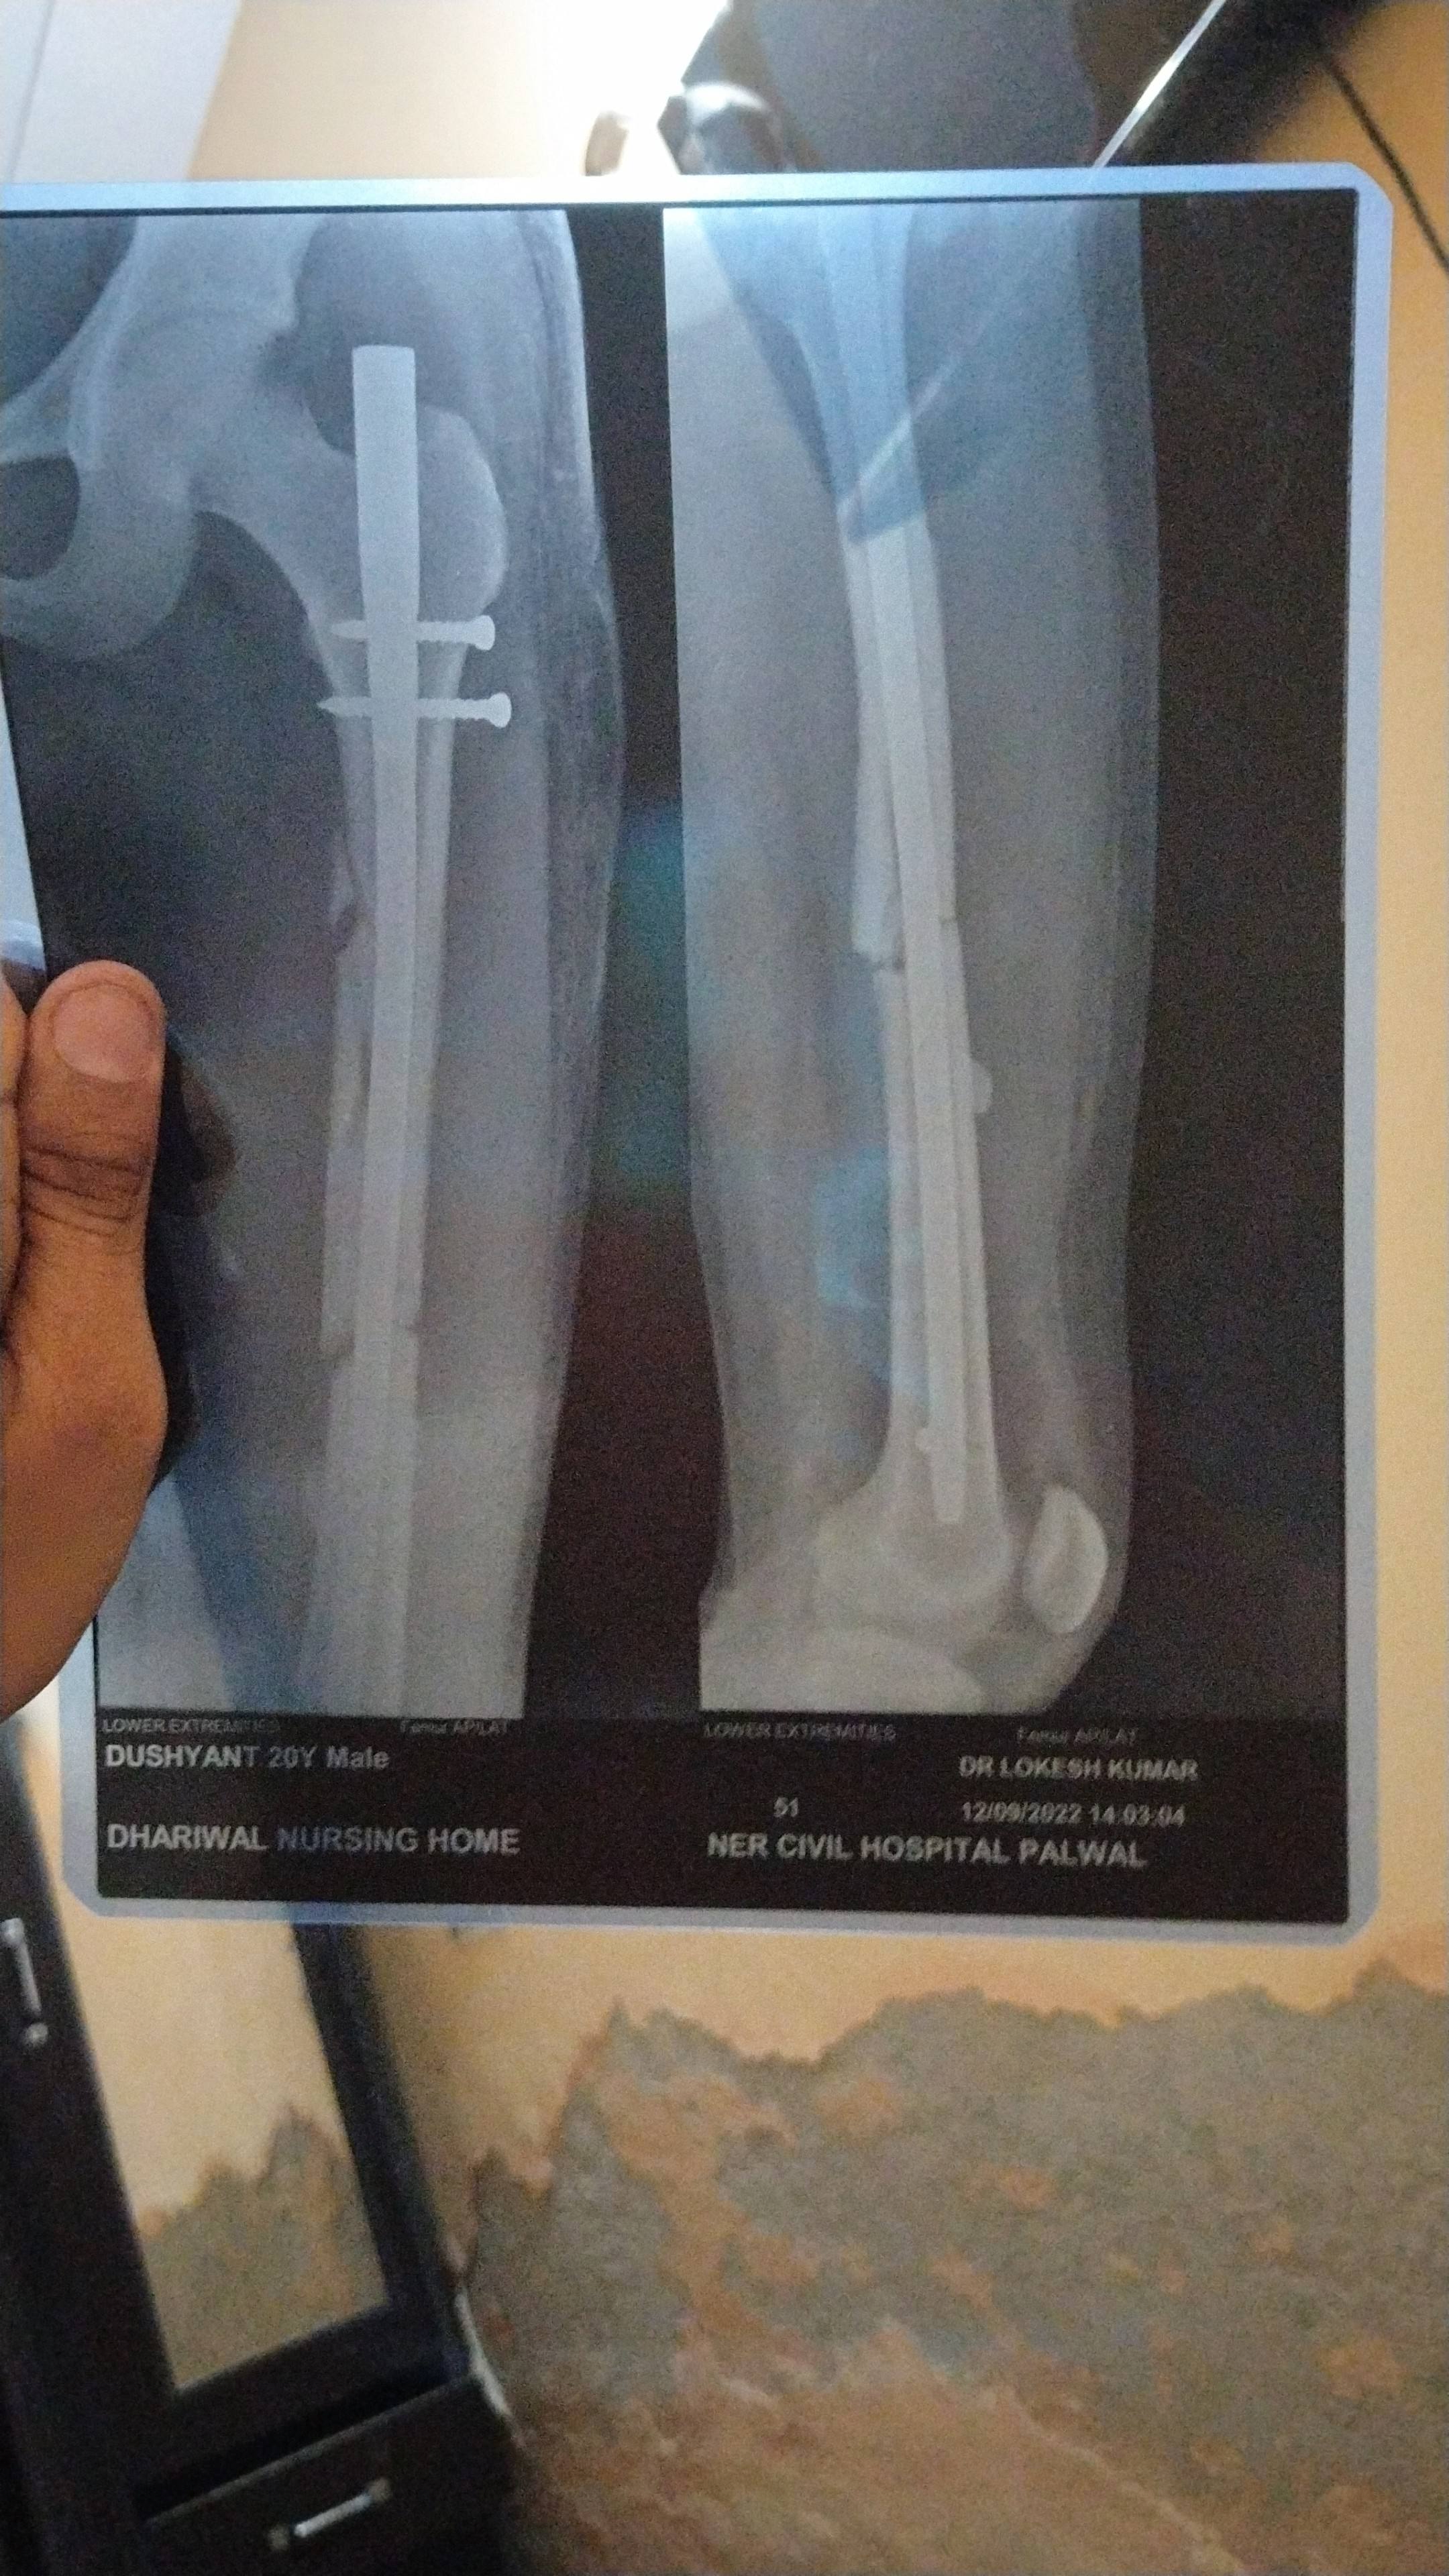

Sir this one is x ray after 5 month 11 days of surgery

will this bone unite or need bone grafting

Age only 20 years

ORIF has been done in this case